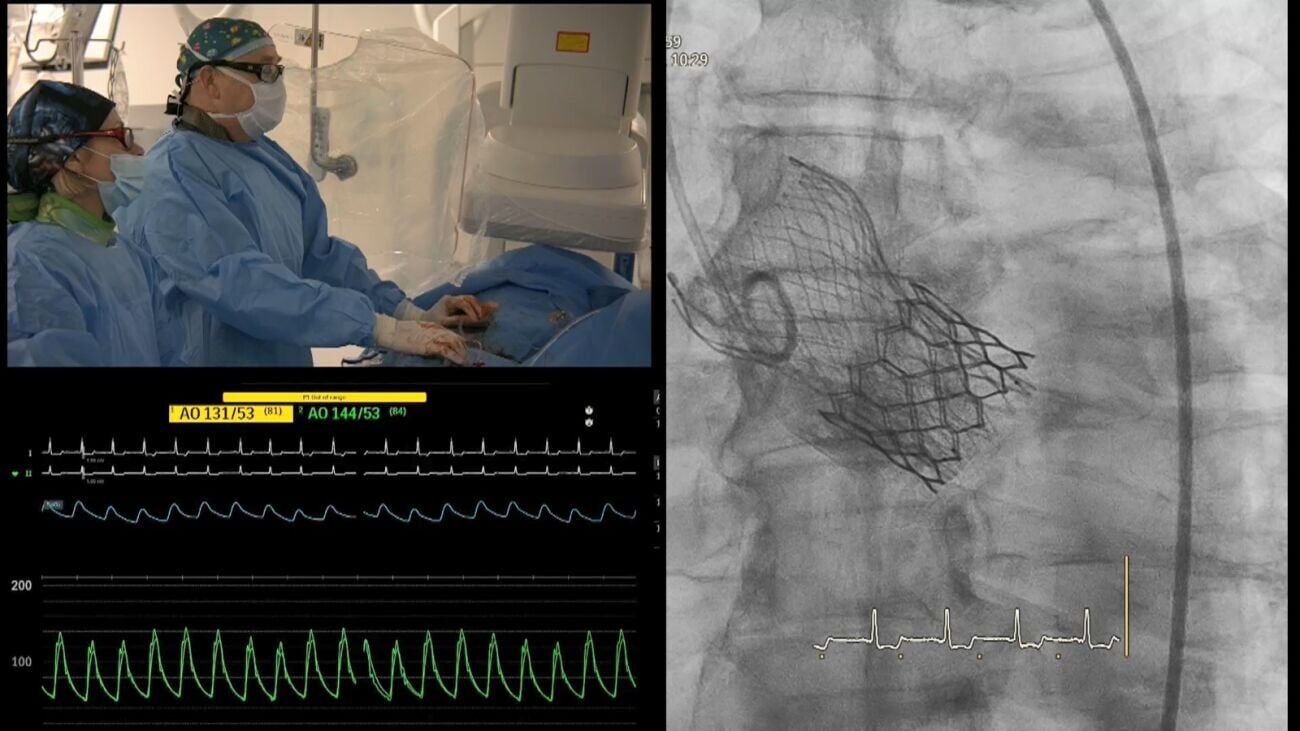

הישג בינלאומי למרכז הרפואי וולפסון בחולון: צוות המערך לקרדיולוגיה פולשנית ביצע צנתור מורכב ששודר לכנס רפואי בהודו

הישג מרשים וגאווה ישראלית למרכז הרפואי וולפסון בחולון: צוות המערך לקרדיולוגיה פולשנית הוכיח השבוע כי מצוינות רפואית אינה יודעת גבולות. חרף המעבר לפעילות בחדר צנתור ממוגן, ביצע הצוות בהצלחה פרוצדורה מורכבת של צנתור מסתם, אשר הוקלטה ושודרה היישר לכנס בינלאומי בנושא צנתורי לב שהתקיים בהודו.

בבית החולים ציינו לשבח את עבודתם של פרופ' דננברג וד"ר מנביץ, מצוות המערך לקרדיולוגיה פולשנית, אשר ביצעו את ההליך המורכב וייצגו את הפנים המקצועיות של המרכז הרפואי ושל הרפואה הישראלית בעולם.